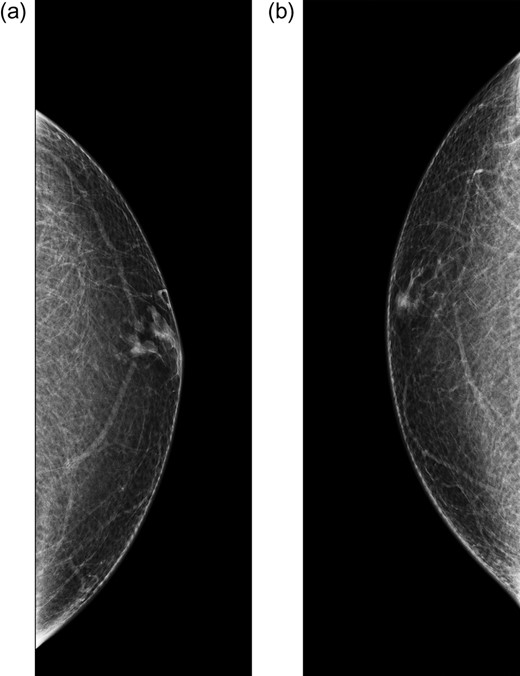

Bilateral mammogram demonstrated mild gynecomastia in both sides with no discrete mass or clusters of microcalcifications (Fig. 1). A follow-up ultrasound around the area of palpable concern did show a prominent duct with irregular contours at the 6:00 position in the left breast (Fig. 2). Excisional biopsy was recommended and a subareolar biopsy of the left breast was performed.

Ultrasound of the left breast at the 6:00 region reveals a mildly hypoechoic mass with ductal extension.